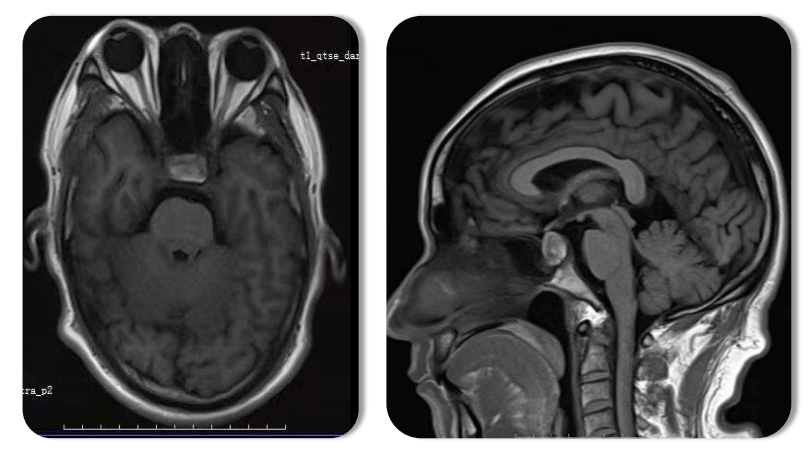

mri片子上垂体腺瘤与周围结构的初步辨认

中年女性,视力下降2 年,巨大垂体瘤

通过磁共振成像检查发现垂体瘤,手术治疗后视力视野均有好转.

手术成功切除巨大垂体腺瘤